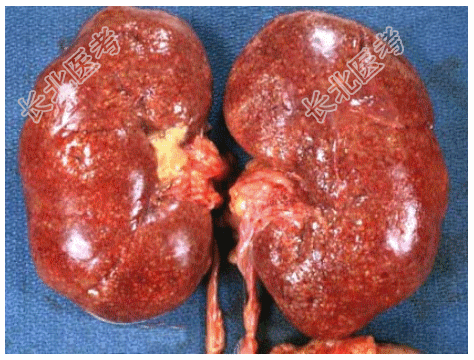

- [材料题] 死者,女性,28岁。因败血症死亡。发病初期曾有持续发热、腰痛、尿频、尿急、脓尿等症状。尸检见双肾肿大,包膜紧张,肾盂肾盏黏膜充血、水肿、表面有脓性分泌物,并可见小脓肿(如图),镜检如图所示。